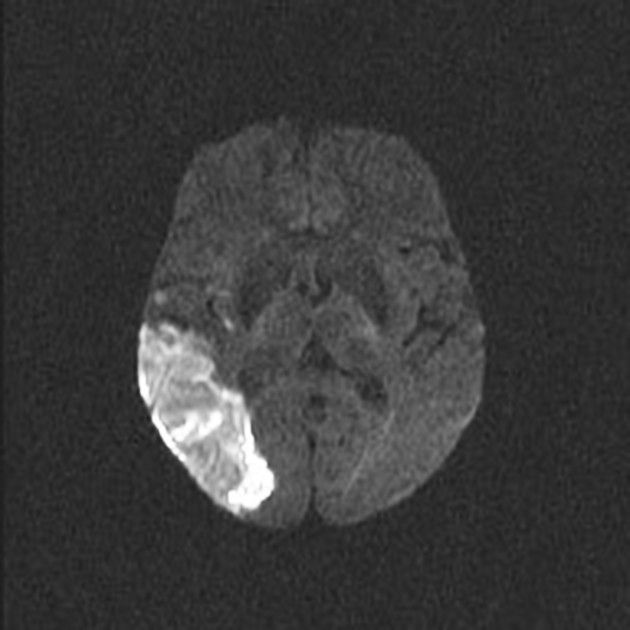

뇌경색 전조증상과 대처방법 및 치료 방법

원인

뇌경색 전조증상은 일시적인 뇌혈류 저하가 원인입니다. 이는 대개 혈압이나 혈관 질환, 고지혈증, 당뇨병, 과음, 금연 등의 생활 습관 등이 원인일 수 있습니다.